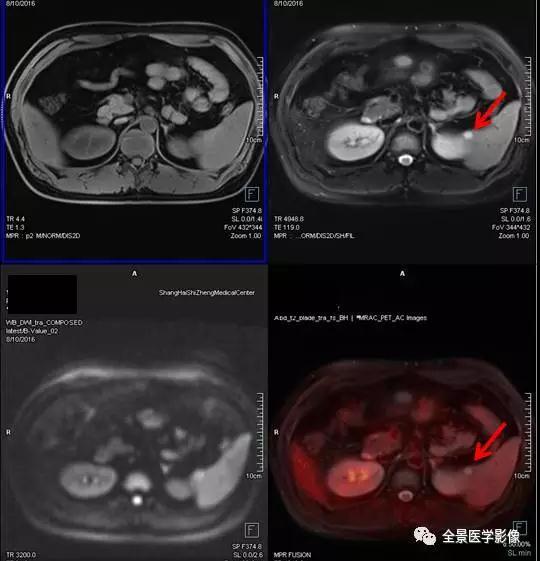

PET/MRI

泌尿系统

肾癌

◆ 案例:老年女性,右下肢胀半年余,右侧卵巢良性肿瘤术后。右肾上部见一长径约 4.5 cm 肿块,FDG 呈本底摄取。手术病理提示肾癌。

点评:

肾癌约占成人恶性肿瘤的 2%~3%,近年来,约 50% 的肾癌是经健康查体时发现的无症状肾癌。有症状的肾癌患者中最常见的症状是腰痛和血尿。对早期肾癌患者可采用微创的保肾手术,对中晚期肾癌患者则采用根治性肾切除术,因此早期发现非常重要。

血管平滑肌脂肪瘤

◆ 案例:中年女性,甲状腺肿瘤术后复查。右肾中部见直径约 2.5 cm 异常信号灶,内含脂肪信号,FDG 无代谢,诊断为血管平滑肌脂肪瘤。

血管平滑肌脂肪瘤 (以往称错构瘤) 是肾良性肿瘤中最常见者,约占肾肿瘤的 3%。肿瘤较小者,可以 B 超定期随访复查; 巨大的肿瘤会压迫邻近脏器,且容易发生出血,引起腹痛等急症,应避免剧烈运动及外伤。

膀胱癌

◆ 案例:老年男性,排尿中断半年余,无血尿。膀胱左后壁局限性增厚,病灶以宽基底与膀胱壁相连,长径约 1.8 cm。膀胱镜证实为膀胱癌。

膀胱癌是泌尿系统最常见的恶性肿瘤,较为明确的两大致病危险因素是吸烟和职业接触芳香胺类物质。绝大多数的膀胱癌患者最初的临床表现是血尿。本例患者无血尿症状,经 PET/MR 检查偶然发现了膀胱内占位病变。